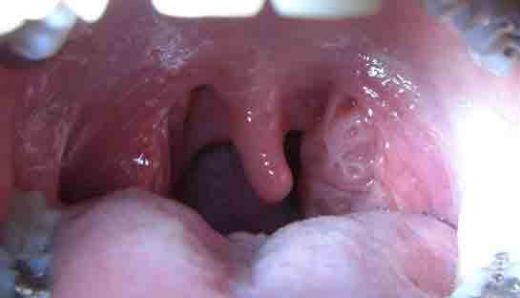

Sol bademcik şişmesi, genellikle boğazın arka kısmında yer alan lenfoid dokunun iltihaplanması veya enfekte olması durumudur. Bademcikler, bağışıklık sisteminin bir parçası olarak, vücut savunmasında önemli bir rol oynamaktadır. Bu durum, çeşitli etkenlerden kaynaklanabilir ve genellikle enfeksiyon belirtisi olarak ortaya çıkar.

Sol bademcik şişmesi yaşadım ve gerçekten rahatsız edici bir durum. Boğazımda ağrı ve yutkunma güçlüğü ile birlikte beyaz lekeler oluştu. Tedavi için doktora başvurdum. Tek taraflı bademcik şişmesi doktor sitesinde de belirttiği gibi önemli bir durum, dikkat edilmesi lazım.

Alpartur, yaşadığın bu durum gerçekten de rahatsız edici olabilir. Boğazdaki ağrı ve yutkunma güçlüğü, günlük yaşamı olumsuz etkileyebilir. Beyaz lekelerin varlığı, enfeksiyon belirtilerine işaret edebilir ve bu nedenle doktora başvurman çok önemli bir adım.

Dikkat Edilmesi Gerekenler

Tek taraflı bademcik şişmesi, bazen daha ciddi durumların bir belirtisi olabileceğinden, doktorun önerilerini dikkatle takip etmekte fayda var. Özellikle ateş, şiddetli ağrı veya nefes alma zorluğu gibi belirtiler varsa, derhal sağlık kuruluşuna başvurmak gerekebilir.